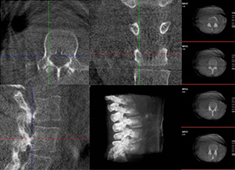

术中三维CT如何辅助手术机器人完成手术导航

手术机器人对术中配准的要求较高,仅依靠其自身的导航定位功能还远远不够,需要结合术中三维CT影像来提高导航精准度。术中三维CT是如何辅助手术机器人完成手术导航的?下面以术中三维移动C臂(PLX C7600)辅助脊柱外科手术...